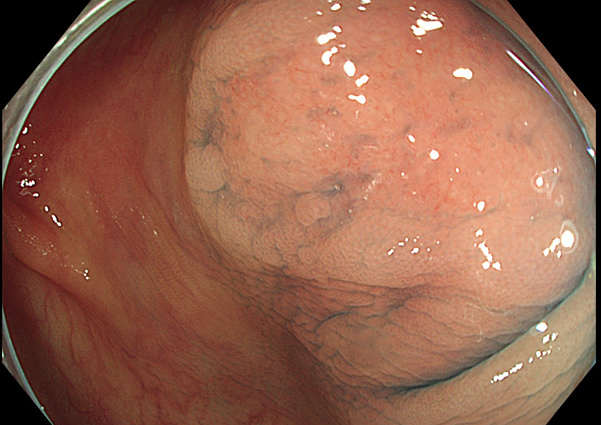

陥凹型過形成ポリープの完全切除

通常の過形成ポリープ・SSAPや腺腫より癌化リスクが高いのでは?という意見があります。

気を付けて観察すると「実は稀ではない」病変なのです